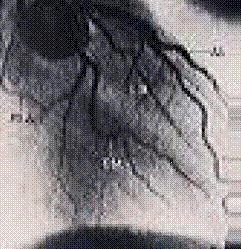

Investigatiile radioizotopice calitative si cantitative permit evaluarea zonelor ischemice si necrozelor miocardice. In acest scop se utilizeaza, in mod uzual, scintigrafia de perfuzie si cea de echilibru. Zonele ischemice in timpul efortului pot fi identificate si cuantificate datorita scaderii cantitatii de izotopi fixate (C. Luca, S. Bradisteanu, C. Sterian, 1996).

Figura 5. Arterele coronare - piese anatomice injectate cu substanta de contrast si radiografiate: a) in vitro; b) la cadavru